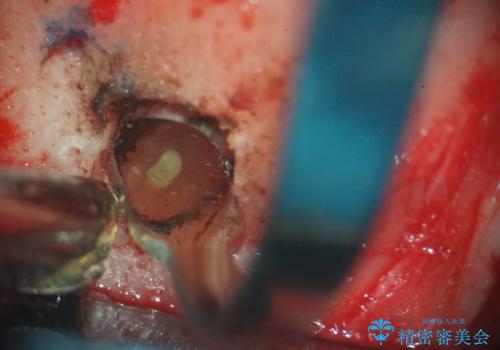

- 歯肉の下まで深く歯が折れたことを主訴に来院された患者様です。

かかりつけ医にて応急的に修復してますが根本的な治療を希望され、矯正的挺出を行ったのち、歯周外科を行い、歯冠修復をしております。

歯肉縁下の水平破折をきちんと治療するためには時間も費用もかかります。